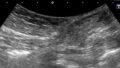

静脈学会HPに掲載されている骨盤静脈疾患のSVP(症状-静脈瘤-病態生理)分類を元に分類方法やエコー操作方法を説明して下さいました。

エコーでは仰臥位と立位で逆流評価をするそうです。症例やレポートも提示して下さり、きれいなエコー画像も拝見できて勉強になりました。